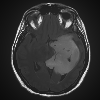

For the first experiment, we consider the image shown in the left panel of Figure 1, which depicts a magnetic resonance image (MRI) of a brain tumour [24, Figure 1B]. The colour distribution of the pixels is displayed in the right panel of the same figure. The output of Algorithm 1 for three different values of the fidelity parameter is reported in Figure 2. As expected, has a decisive influence on the optimisation outcome. For large values of , the reconstruction closely follows the original image, and three distinct clusters emerge, corresponding to the background, healthy brain tissue, and tumour. For intermediate values, we observe a distinctive blurring effect caused by the penalisation of colour variation; consequently, edges are not well preserved. For smaller values of , the gradient term dominates, and global interactions drive the agents to consensus, producing a single cluster that represents the average colour of the image.

The first test is carried out on the MRI scan in Figure 1, on which Algorithm 1 works best. The results are shown in Figure 5. Despite finding qualitatively similar controls, reported on the bottom row, the healthy brain tissue and the tumour are depicted as more uniform clusters by Algorithm 2, without detailing them excessively, and at the same time without any blurring.